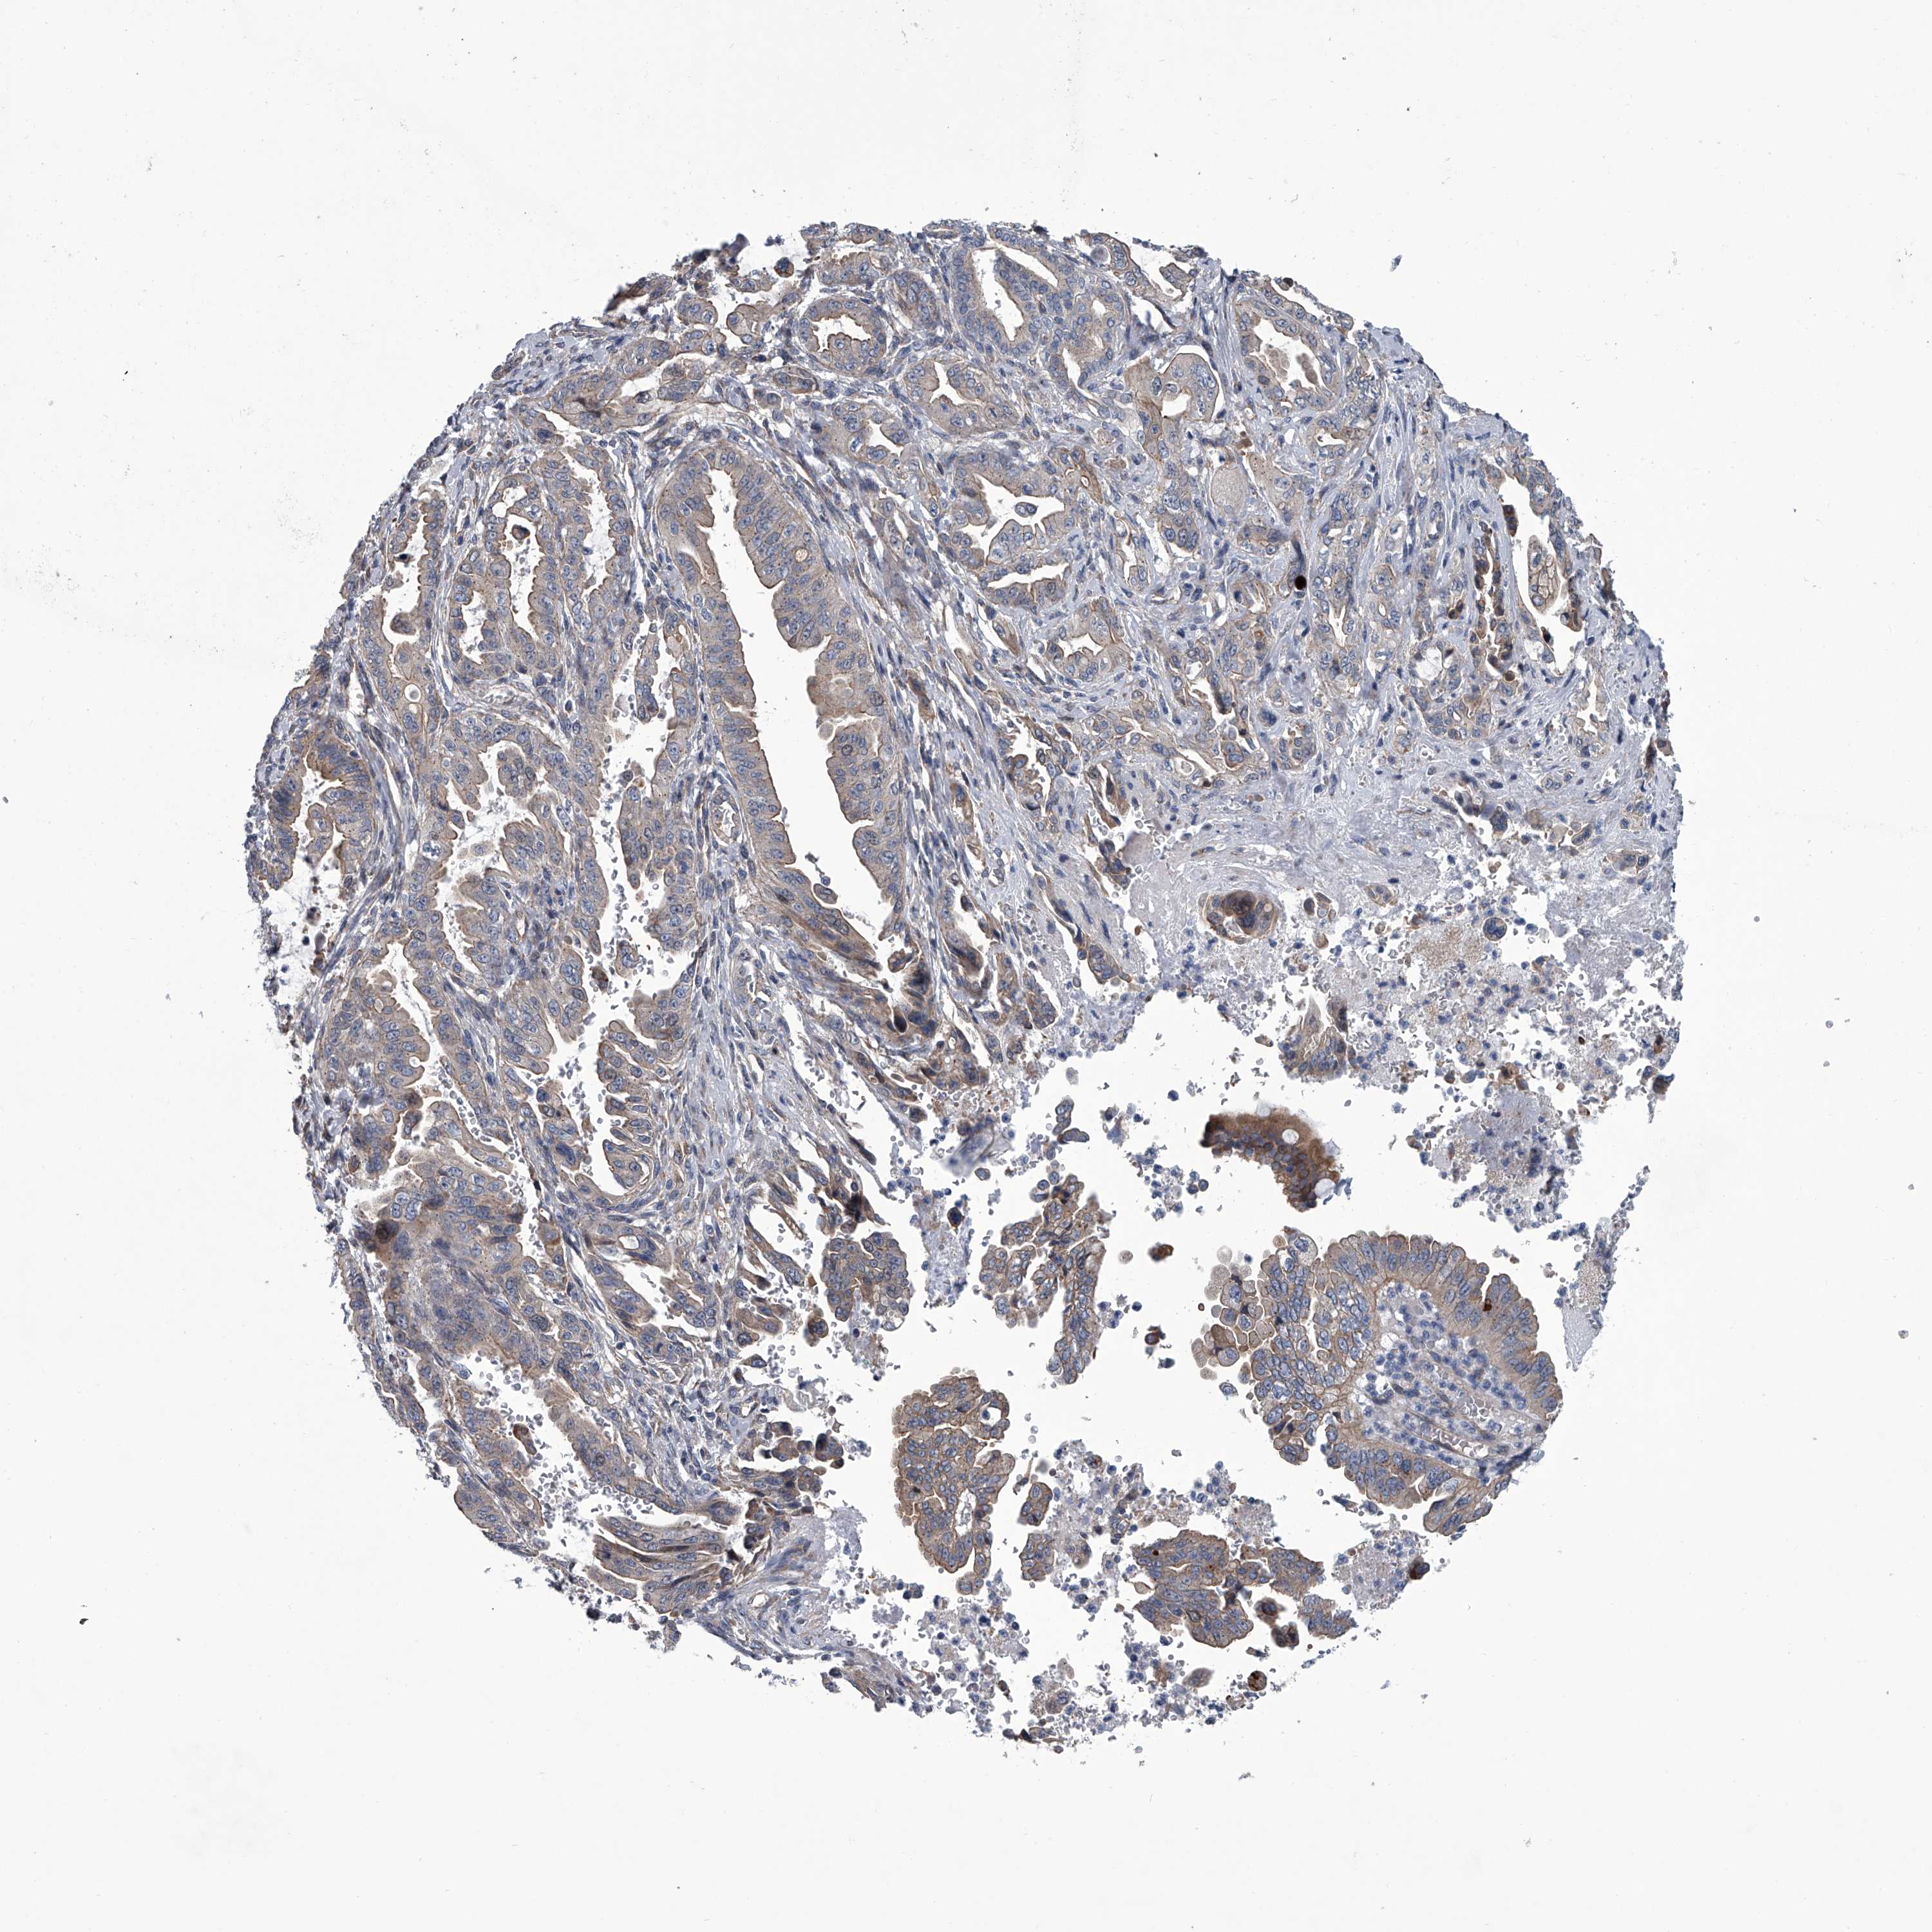

PANCREATIC CANCER - Protein expressioni

A mouse-over function shows sample information and annotation data. Click on an image to view it in a full screen mode. Samples can be filtered based on level of antibody staining by selecting one or several of the following categories: high, medium, low and not detected. The assay and annotation is described here.

Note that samples used for immunohistochemistry by the Human Protein Atlas do not correspond to samples in the TCGA dataset.

Antibody stainingi

Antibody staining in the annotated cell types in the current human tissue is reported as not detected, low, medium, or high, based on conventional immunohistochemistry profiling in selected tissues. This score is based on the combination of the staining intensity and fraction of stained cells.

Each image is clickable and will lead to virtual microscopy that enables deeper exploration of all samples and also displays staining intensity scores, fraction scores and subcellular localization as well as patient and tissue information for each sample.

Antibody HPA031470

Antibody HPA031471

Staining

High

Medium

Low

Not detected

Intensity

Strong

Moderate

Weak

Negative

Quantity

>75%

75%-25%

<25%

None

Location

Nuclear

Cytoplasmic/membranous

Cytoplasmic/membranous,nuclear

Adenocarcinoma, NOS